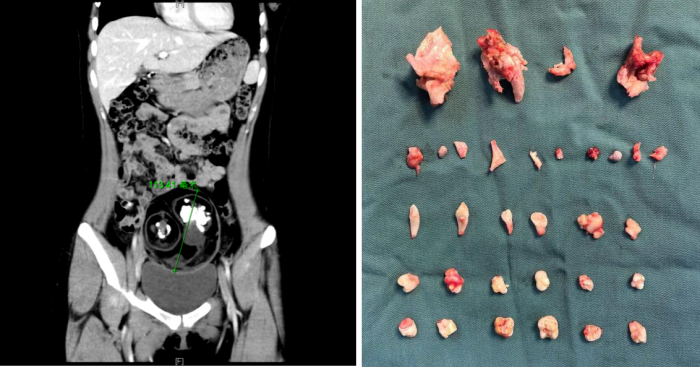

一听说要手术,年仅18岁的曾琳琳非常恐惧,她担心手术的疼痛,也害怕腹部会留下明显的疤痕影响美观。面对琳琳的担忧,魏馨和团队经过充分的术前评估与讨论,为她量身定制了“经脐单孔腹腔镜手术”的治疗方案。手术由魏馨主刀,凭借精湛的技术和丰富的经验,团队通过这唯一的肚脐切口,成功将直径12厘米的畸胎瘤完整无损地剥离并取出。术后清点肿瘤内容物时,连医护人员都感到惊讶:里面竟然包含了24颗形态各异的牙齿,以及最大直径接近5厘米的骨骼组织。

CT检查示下腹部有一直径约12厘米的肿块 术中清理出来的肿瘤内容物(含牙齿、骨骼)